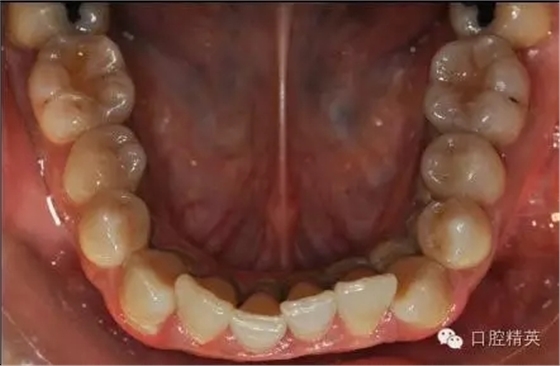

本病例 :女 34歲,主訴刷牙出血,覺(jué)牙齒輕度松動(dòng)一年。

檢查見(jiàn)大量齦上及齦下結(jié)石,探診出血,牙周袋較深,32-42 II度松動(dòng)。X線片顯示牙槽骨水平吸收。

診斷:成人慢性廣泛性中度牙周炎。

治療計(jì)劃:口腔衛(wèi)生宣教,刷牙指導(dǎo),齦上潔治,齦下刮治術(shù),下頜牙33-43牙周固定。

治療前: